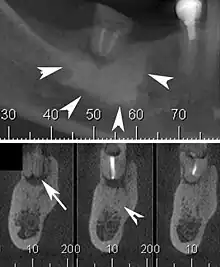

Cone beam CT scan presenting a diffuse hyperdense lesion in the apex of a mandibular molar (arrowhead, top) adjacent to an inflammatory periapical lesion (arrow, bottom).[1]

Condensing osteitis is a periapical inflammatory disease that results from a reaction to a dental related infection. This causes more bone production rather than bone destruction in the area (most common site is near the root apices of premolars and molars). The lesion appears as a radiopacity in the periapical area hence the sclerotic reaction. The sclerotic reaction results from good patient immunity and a low degree of virulence of the offending bacteria. The associated tooth may be carious or contains a large restoration, and is usually associated with a non-vital tooth. It was described by Dr. Carl Garré in 1893.